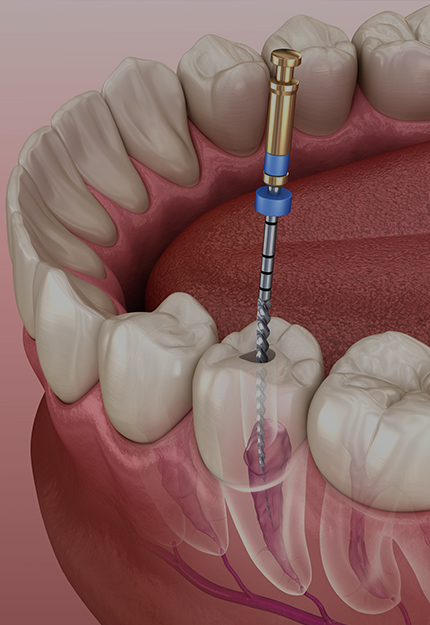

• 엔도

근관 성형을 하면서 실시간 근관장 측정이 가능, 정확한 RPM과 토크 출력으로 안정적인 시술이 가능